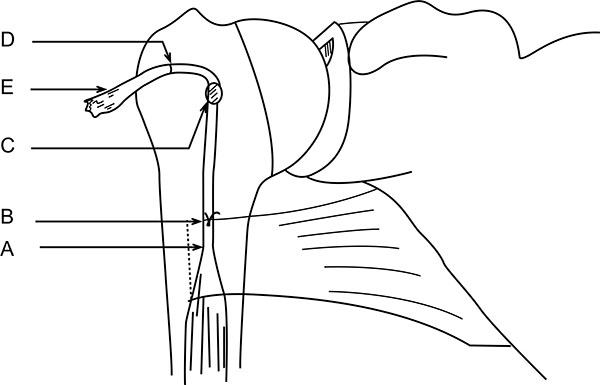

Now, the tendon end to the DBG is retrieved using the smallest size Foleys catheter. Keep the tendon over the tunnel, without any kinking, and mark (C) on the tendon at DBG (Fig. 6). Make another mark (D) on the tendon at a distance equal to measured tunnel depth (TD) (Fig. 6). Hence, the required tendon length for this procedure is A-D (Fig. 6). The tendon is resected at mark D. Now, the tendon end is pulled back through distal incision for suturing. This is because it is easy to suture the tendon when we have enough length of tendon to hold and know the rotational alignment of the tendon.

A number-5 synthetic polyester suture (Ethibond Excel, Ethicon Inc; Johnson and Johnson, USA) is woven into the proximal biceps tendon using the Krackow technique or whipstitch suture technique (Fig. 3D). The tendon end to the DBG is retrieved again using the smallest size Foleys catheter (Fig. 3E). We used a 4-holed Endo Button without continuous loop (4.0 mm × 12 mm Endo-Button CL Ultra, Smith and Nephew, Andover, MA, USA). One limb of suture from the tendon end was threaded through the central two holes of the Endo Button (inside out – outside in). The other suture end from the tendon was passed through the terminal two holes of the Endo Button in a reverse manner i.e. from outside in – inside out (Figs. 4D, 7, 3F). It is important to make certain that the suture limbs are not tangled.

The Endo Button is loaded onto the Button deployment device and passed through bone tunnel (Figs. 4E, 3G). Once the button clears the posterior cortex, the deployment instrument can be removed while the button deploys itself, locking into place on the posterior cortex. Pulling on the sutures shuttles the LHB tendon into the humerus. The sutures are tensioned until the tendon is in contact with the posterior cortex (Fig. 3H). Finally, we advocate using a free needle to pass one suture through the tendon and tie down to the second suture to reinforce the fixation (Figs. 4F, 3I).

Unlike the use of the Biceps Button in the elbow, an additional interference screw is not required to achieve adequate fixation of the tendon. Rather, an additional suture is passed through the tendon of the LHB once it is shuttled through the humerus. This provides additional fixation strength to withstand physiologic loads. At this stage, cut the stay suture applied at superior border of pectoralis major tendon to complete the procedure. Intra-operative radiograph are taken to confirm the position of Endo Button. Wound wash is given and closed in layers. Cuff and collar is applied to support the arm for the first two weeks. Postoperative radiographs were obtained to assess the tenodesis location (Fig. 8A).